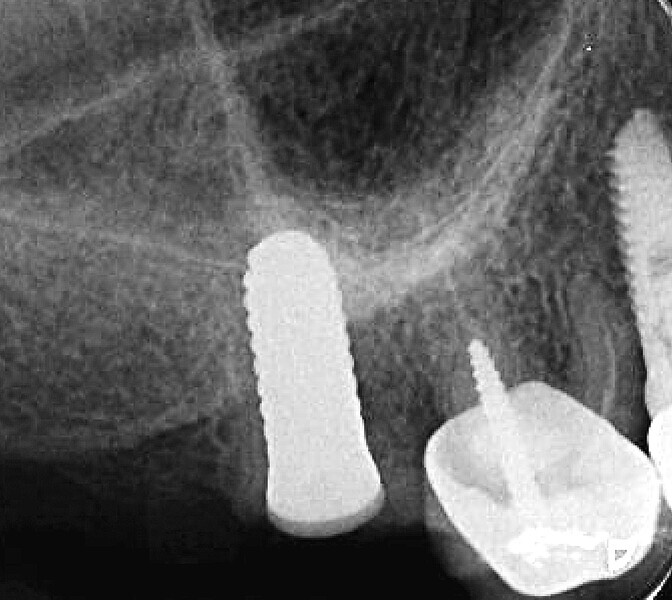

Fig. 44 : Radiographie de contrôle et excellente intégration de l’implant en céramique dans l’environnement parodontal.

Fig. 45 : Radiographie de contrôle et excellente intégration de l’implant en céramique dans l’environnement parodontal.

Un patient présentant un défaut infraosseux s’est présenté au cabinet dentaire avec le souhait explicite d’un traitement par un implant en zircone, pour remplacer l’une de ses molaires. Un implant deux pièces en zircone a donc été posé et le défaut infra-osseux a été traité dans le même temps, au moyen d’une allogreffe osseuse et du dérivé de matrice amélaire Emdogain (Straumann). La mise en charge n’a pas été réalisée à ce stade (Figs. 35–45).